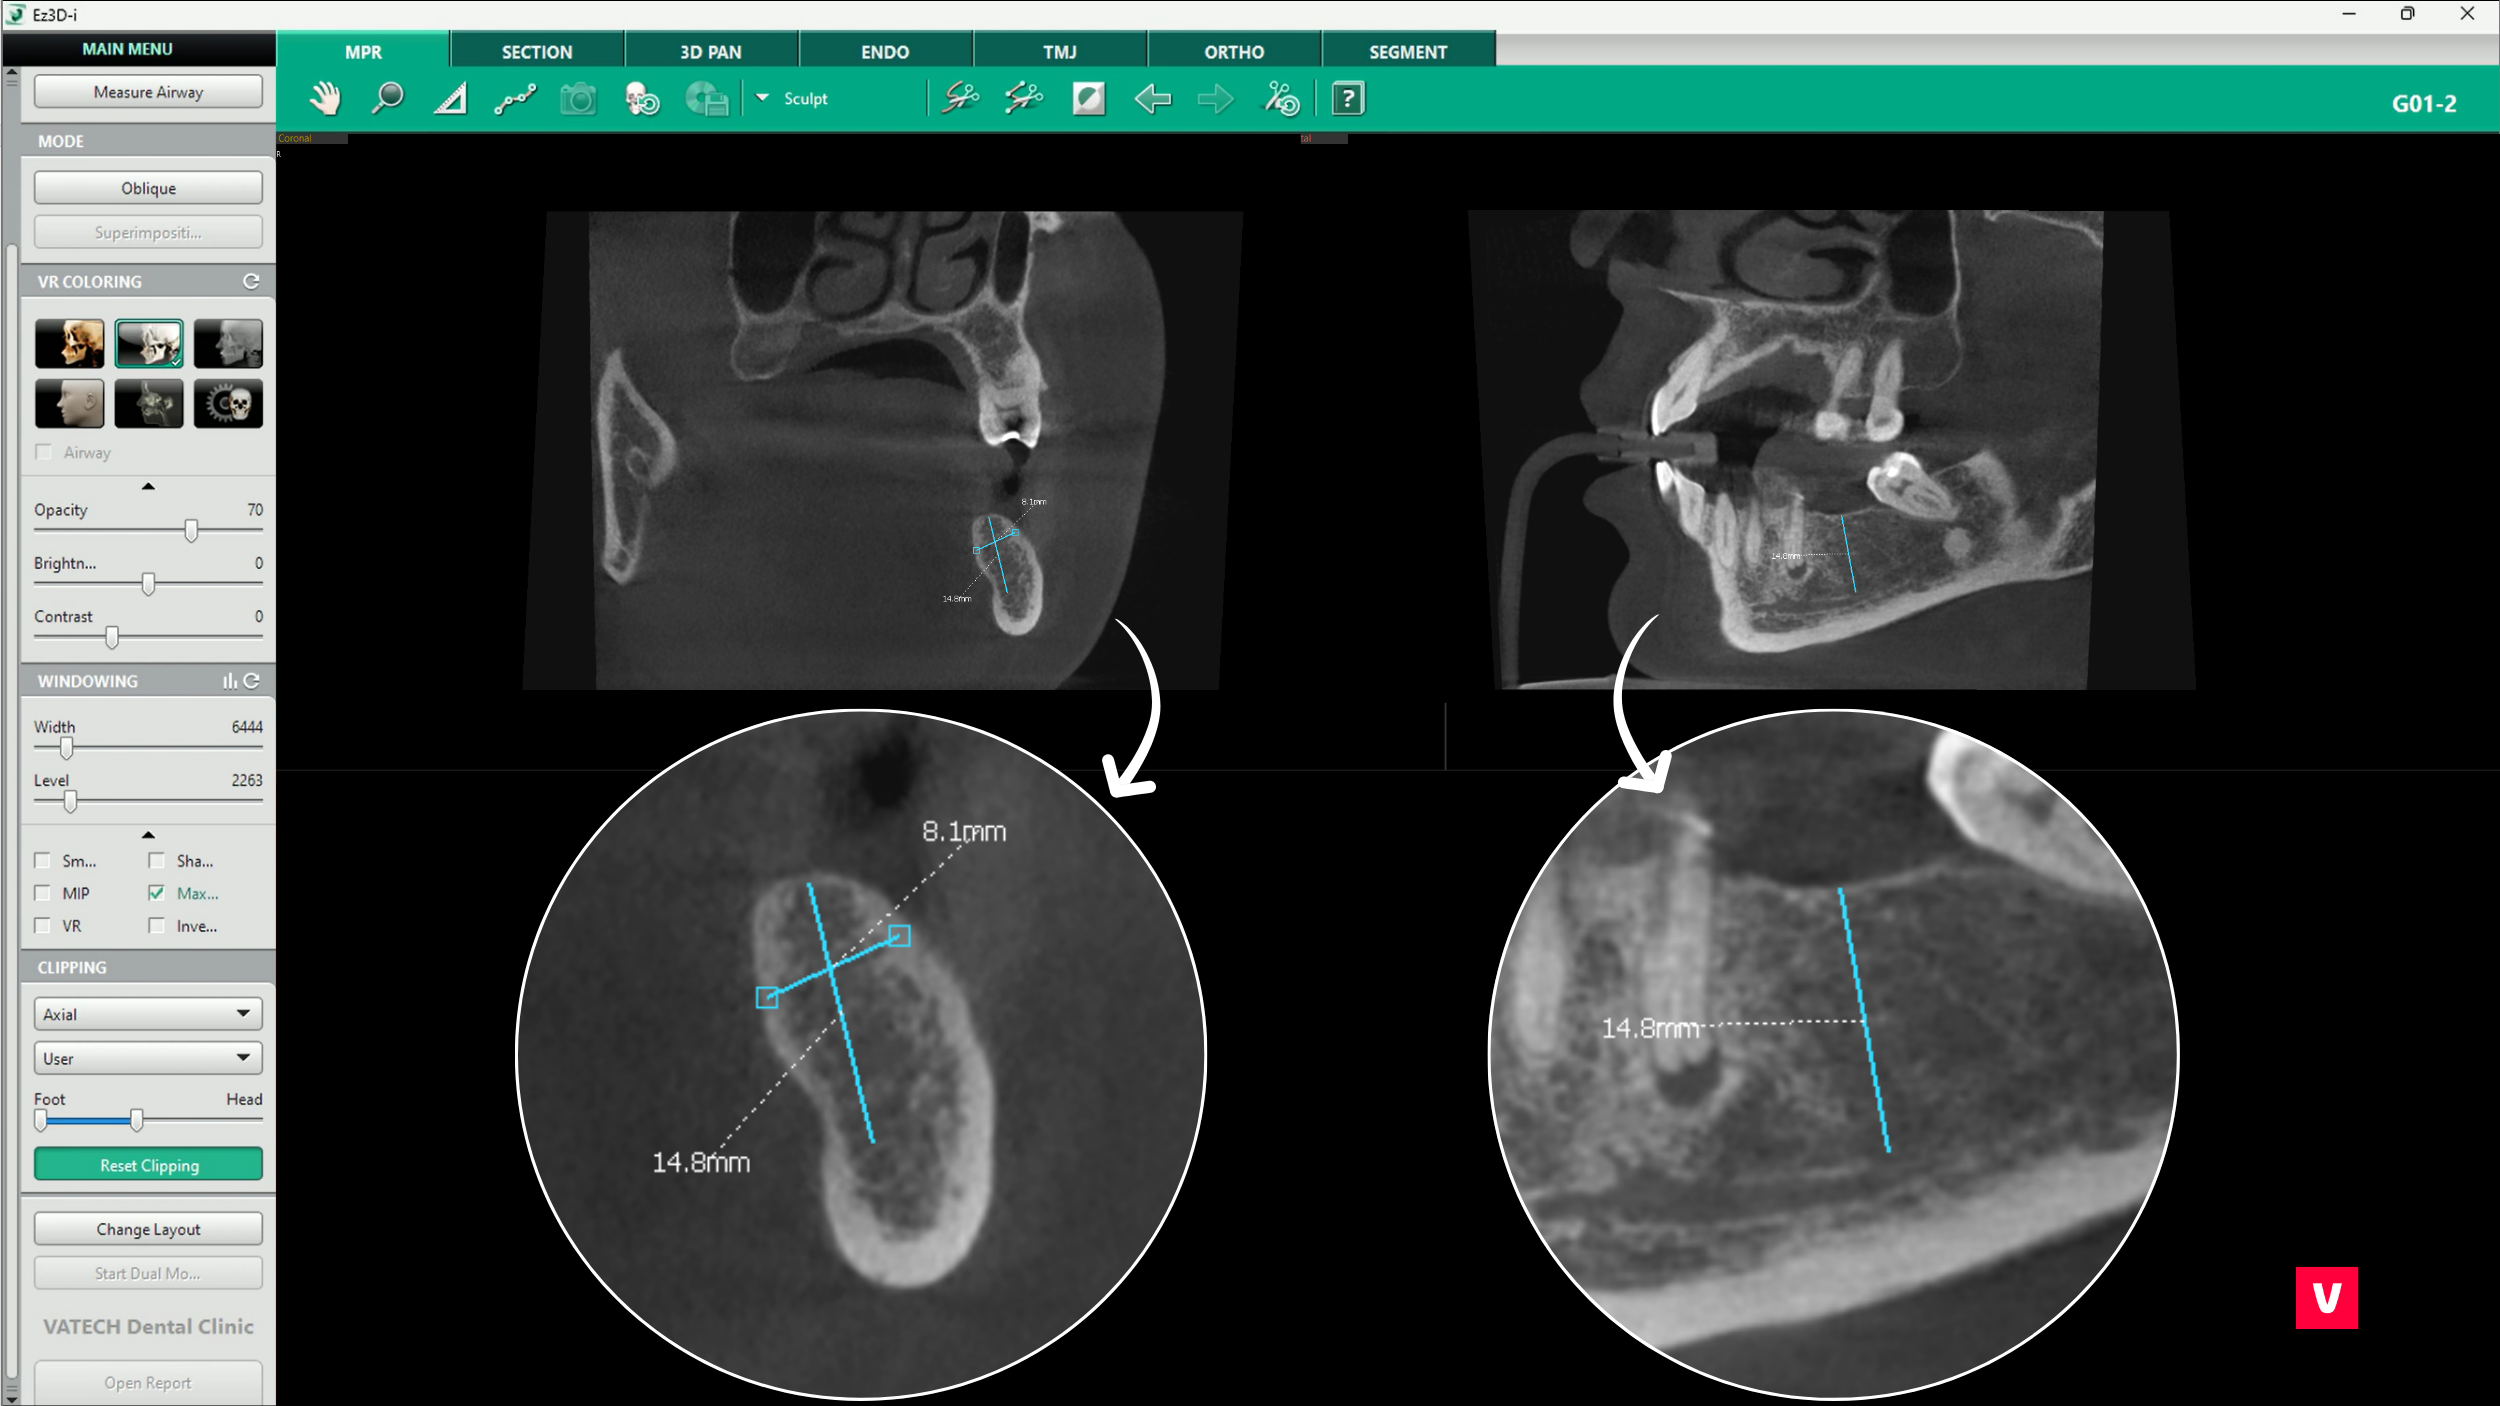

În acest caz particular, s-au folosit trei funcții principale furnizate de software-ul Vatech, Ez3D-i

1. Decuparea

2. „Dublu click”

3. Măsurătorile

Decuparea este o funcție excelentă pentru tăierea imaginii 3D și descoperirea structurilor anatomice ascunse. Aceasta poate ajuta la găsirea problemelor pe care imaginile OPG ar putea să nu le detecteze.

Există 3 planuri diferite de observare: axial, coronal și sagital. De asemenea, decuparea inteligentă este un instrument AI convenabil care ajustează automat planul vizualizat în imaginea 3D în funcție de unghiul de vizualizare.

În cazul de față, medicul a folosit tăierea pe un plan axial pentru a privi în os. Cu această funcție, este foarte ușor să descoperi orice structuri ascunse și să previi potențialele complicații.

2. Dublu click

Funcția „dublu click” oferă un avantaj superior în fluxul de lucru, deoarece te ajută să găsești informațiile necesare prin zoom inteligent. Aceasta înseamnă că dacă găsim zona problematică din imaginea 3D și facem dublu click pe ea, funcția asistată de AI (inteligență artificială) va recunoaște automat același loc în toate planurile. Acest lucru permite o diagnosticare mult mai rapidă și fără erori.

Este una dintre multele comenzi rapide utile pe care le oferă software-ul Ez3D-i de la Vatech.

În abordarea diferitelor probleme de diagnostic, măsurătorile sunt extrem de utile pentru stomatologi. O măsurare adecvată poate face adesea diferența dintre o complicație nediagnosticată corect și un tratament de succes.

Din păcate, imaginile OPG nu oferă întotdeauna informațiile necesare pentru măsurarea corectă, iar distanța poate fi destul de distorsionată. Însă, distorsiunea nu este o îngrijorare pentru utilizatorii Ez3D-i, deoarece software-ul este echipat cu mai multe opțiuni de măsurare diferite, cum ar fi măsurarea lungimii, a lungimii multiple, a unghiurilor sau a razei unui cerc. Toate aceste funcții pot fi realizate cu ajutorul informațiilor adunate în timpul scanării 3D, astfel încât precizia lor este mult mai mare.

După cum se poate observa în acest studiu de caz prezentat, dintele ascuns în maxilar este mult mai aproape decât pare la o scanare OPG obișnuită. Acest lucru ar putea cauza unele probleme în timpul procedurilor stomatologice. Medicul stomatolog a identificat anomalia la timp, prevenind astfel complicațiile.